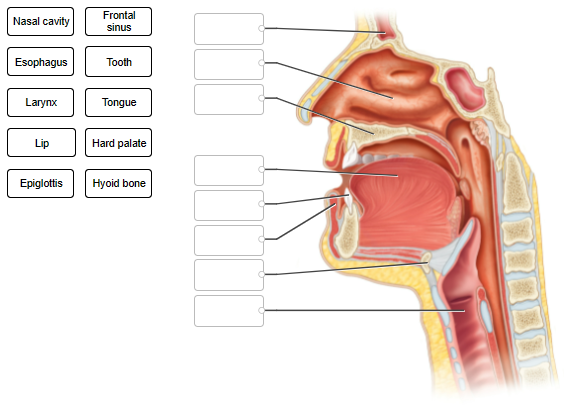

Label the features of the head and neck in the midsagittal section.

Label the tonsils in this midsagittal section

What structure is pulled upward during swallowing to close the opening between the nasal cavity and pharynx?

uvula